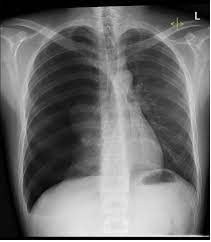

Investigations for pneumothorax

- Chest X-ray

- Sharply defined edge of the deflated lung with complete translucency

- Extent of any mediastinal displacement and reveal any pleural fluid or underlying pulmonary disease.